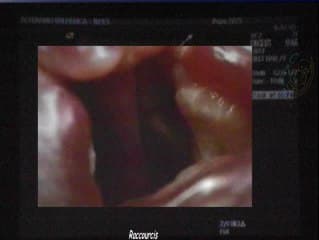

L'auteur montre la technique de mise au point pour diagnostiquer un palais postérieur normal ou pathologique. Il montre les éléments séméiologiques : arcade dentaire, palais postérieur et apophyse à pterygoidess ai su que de nombreuses images en 2D et 3D des différents defects avec fentes palatines alvéolaires , Pierre Robin. Il démontre que l'examen en 2D est suffisant en dépistage.